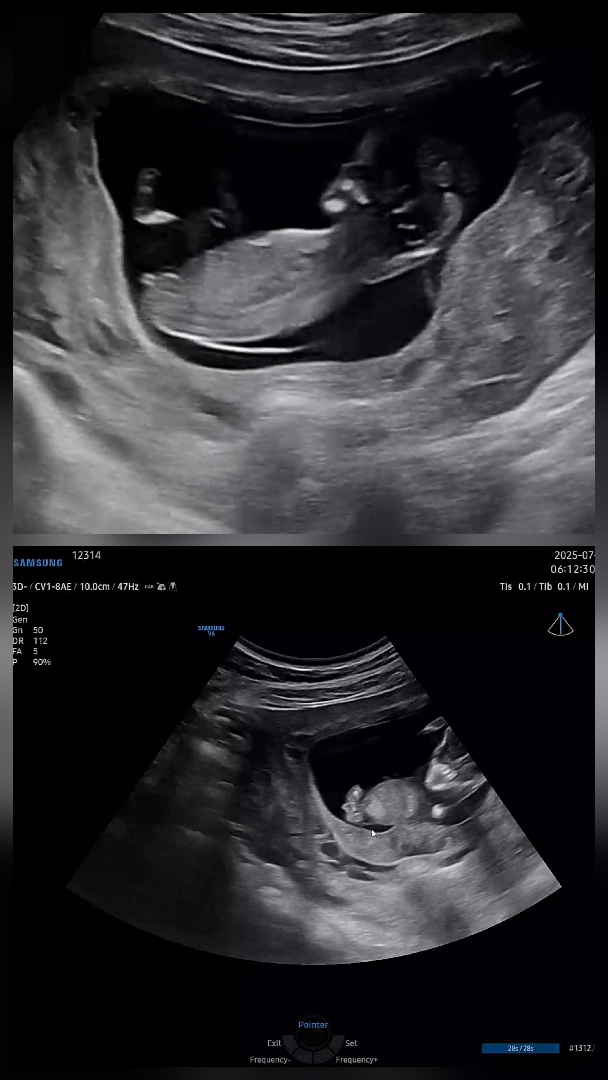

여아 남아 모두 12주엔 생식기가 비슷하게 생겼죠??

그런 글과 사진을 본 것 같은데 다리 사이가 매끈해질 가능성이 있을까요? 각도법 이런건 너무 어렵네요..지금 12주인데 성별 예측 될까요?ㅜㅜㅜ

아들같아용..!